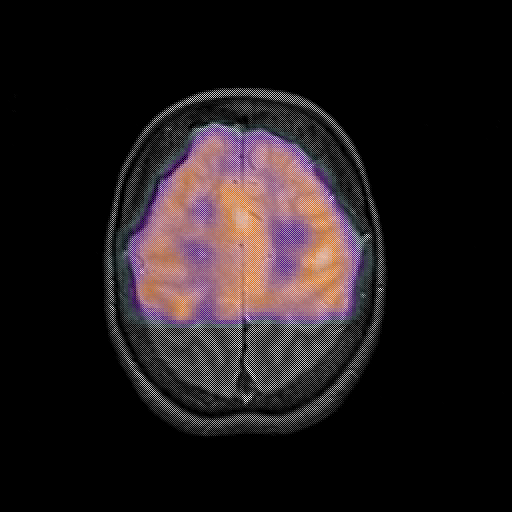

overlay : Slice 41

Slice 41

MRCBFCBF with

T1PDT2T1PDT2